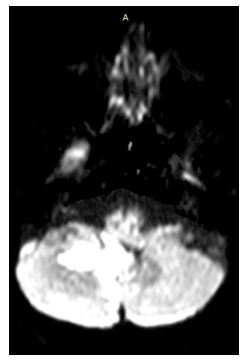

En este caso, el paciente bajo el protocolo HINTS tiene head impulse test con sacadas bilaterales, aunque posible, es muy improbable que haya una disfunción vestibular periférica bilateral al unísono, el nistagmo izquierdo a la maniobra de head shake podría indicar un componente de asimetría vestibular periférica, pero también podría ayudar a realizar diangóstico de infartos de la arteria cerebelosa antero inferior(5) (AICA). Posteriormente encontramos un nistagmo evocado a la mirada, VOR no cancelado, estos últimos dos relacionados a lesión en el flóculo cerebeloso, sacadas hipométricas relacionadas a lesiones en el vermis(4), y otros signos cerebelosos como disdiadococinesia, que orientan más a una patología de origen central, por lo que se solicitó estudio de resonancia magnética contrastado.

Se solicita resonancia magnética que reporta preservación de la sustancia gris-blanca, surcos, cisuras y espacios de amplitud normal, se observan lesiones hiperintensas en la sustancia blanca profunda en secuencias T2 y FLAIR correspondiente a zona del flóculo principalmente derecho, vermis y parte posteromedial de lóbulo cerebeloso posterior derecho y posterior izquierdo, además de zonas de malasia en ambos hemisferios cerebelosos.

Imagen 3, 4 y 5: Secuencia FLAIR con lesiones hiperintensas correspondiente a zona del flóculo principalmente derecho, vermis y parte posteromedial de lóbulo cerebeloso posterior derecho y posterior izquierdo.